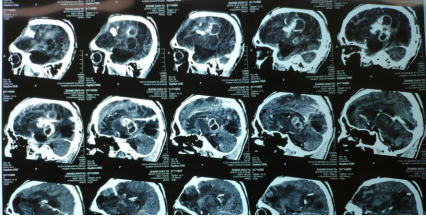

近日,傅继弟教授颅内感染团队(以下称该团队),接诊了一名外省转来的危重颅内感染患者。该患者男性,27岁,3年前因脑外伤后继发性脑积水,行双侧侧脑室分流手术,随后继发颅内感染,反复发热长达3年,颅内出现多达6个脓肿!

患者被120送至该团队时已经昏迷并出现脑疝,呼吸循环开始衰竭。此时他脑内有2根分流管,且与6个脑脓肿粘连,此类手术风险极高!此分流合并颅内感染病例,目前国内外也少见报道。6个脓肿如何处理?2根粘连的分流管如何取出?患者能否度过危险期?能否清醒?

面对这些巨大的压力和挑战,该团队经过快速讨论后,随即制定了详细的手术方案。经过7个小时的显微手术,6个脑脓肿、2根严重粘连的分流管均被取出!

为了彻底清除感染病灶,防止感染复发,该团队采用了创新的手术方式,即将感染的“分流管隧道”一并手术取出并清理了隧道内的积脓,目前该手术方式在国尚未见报道。